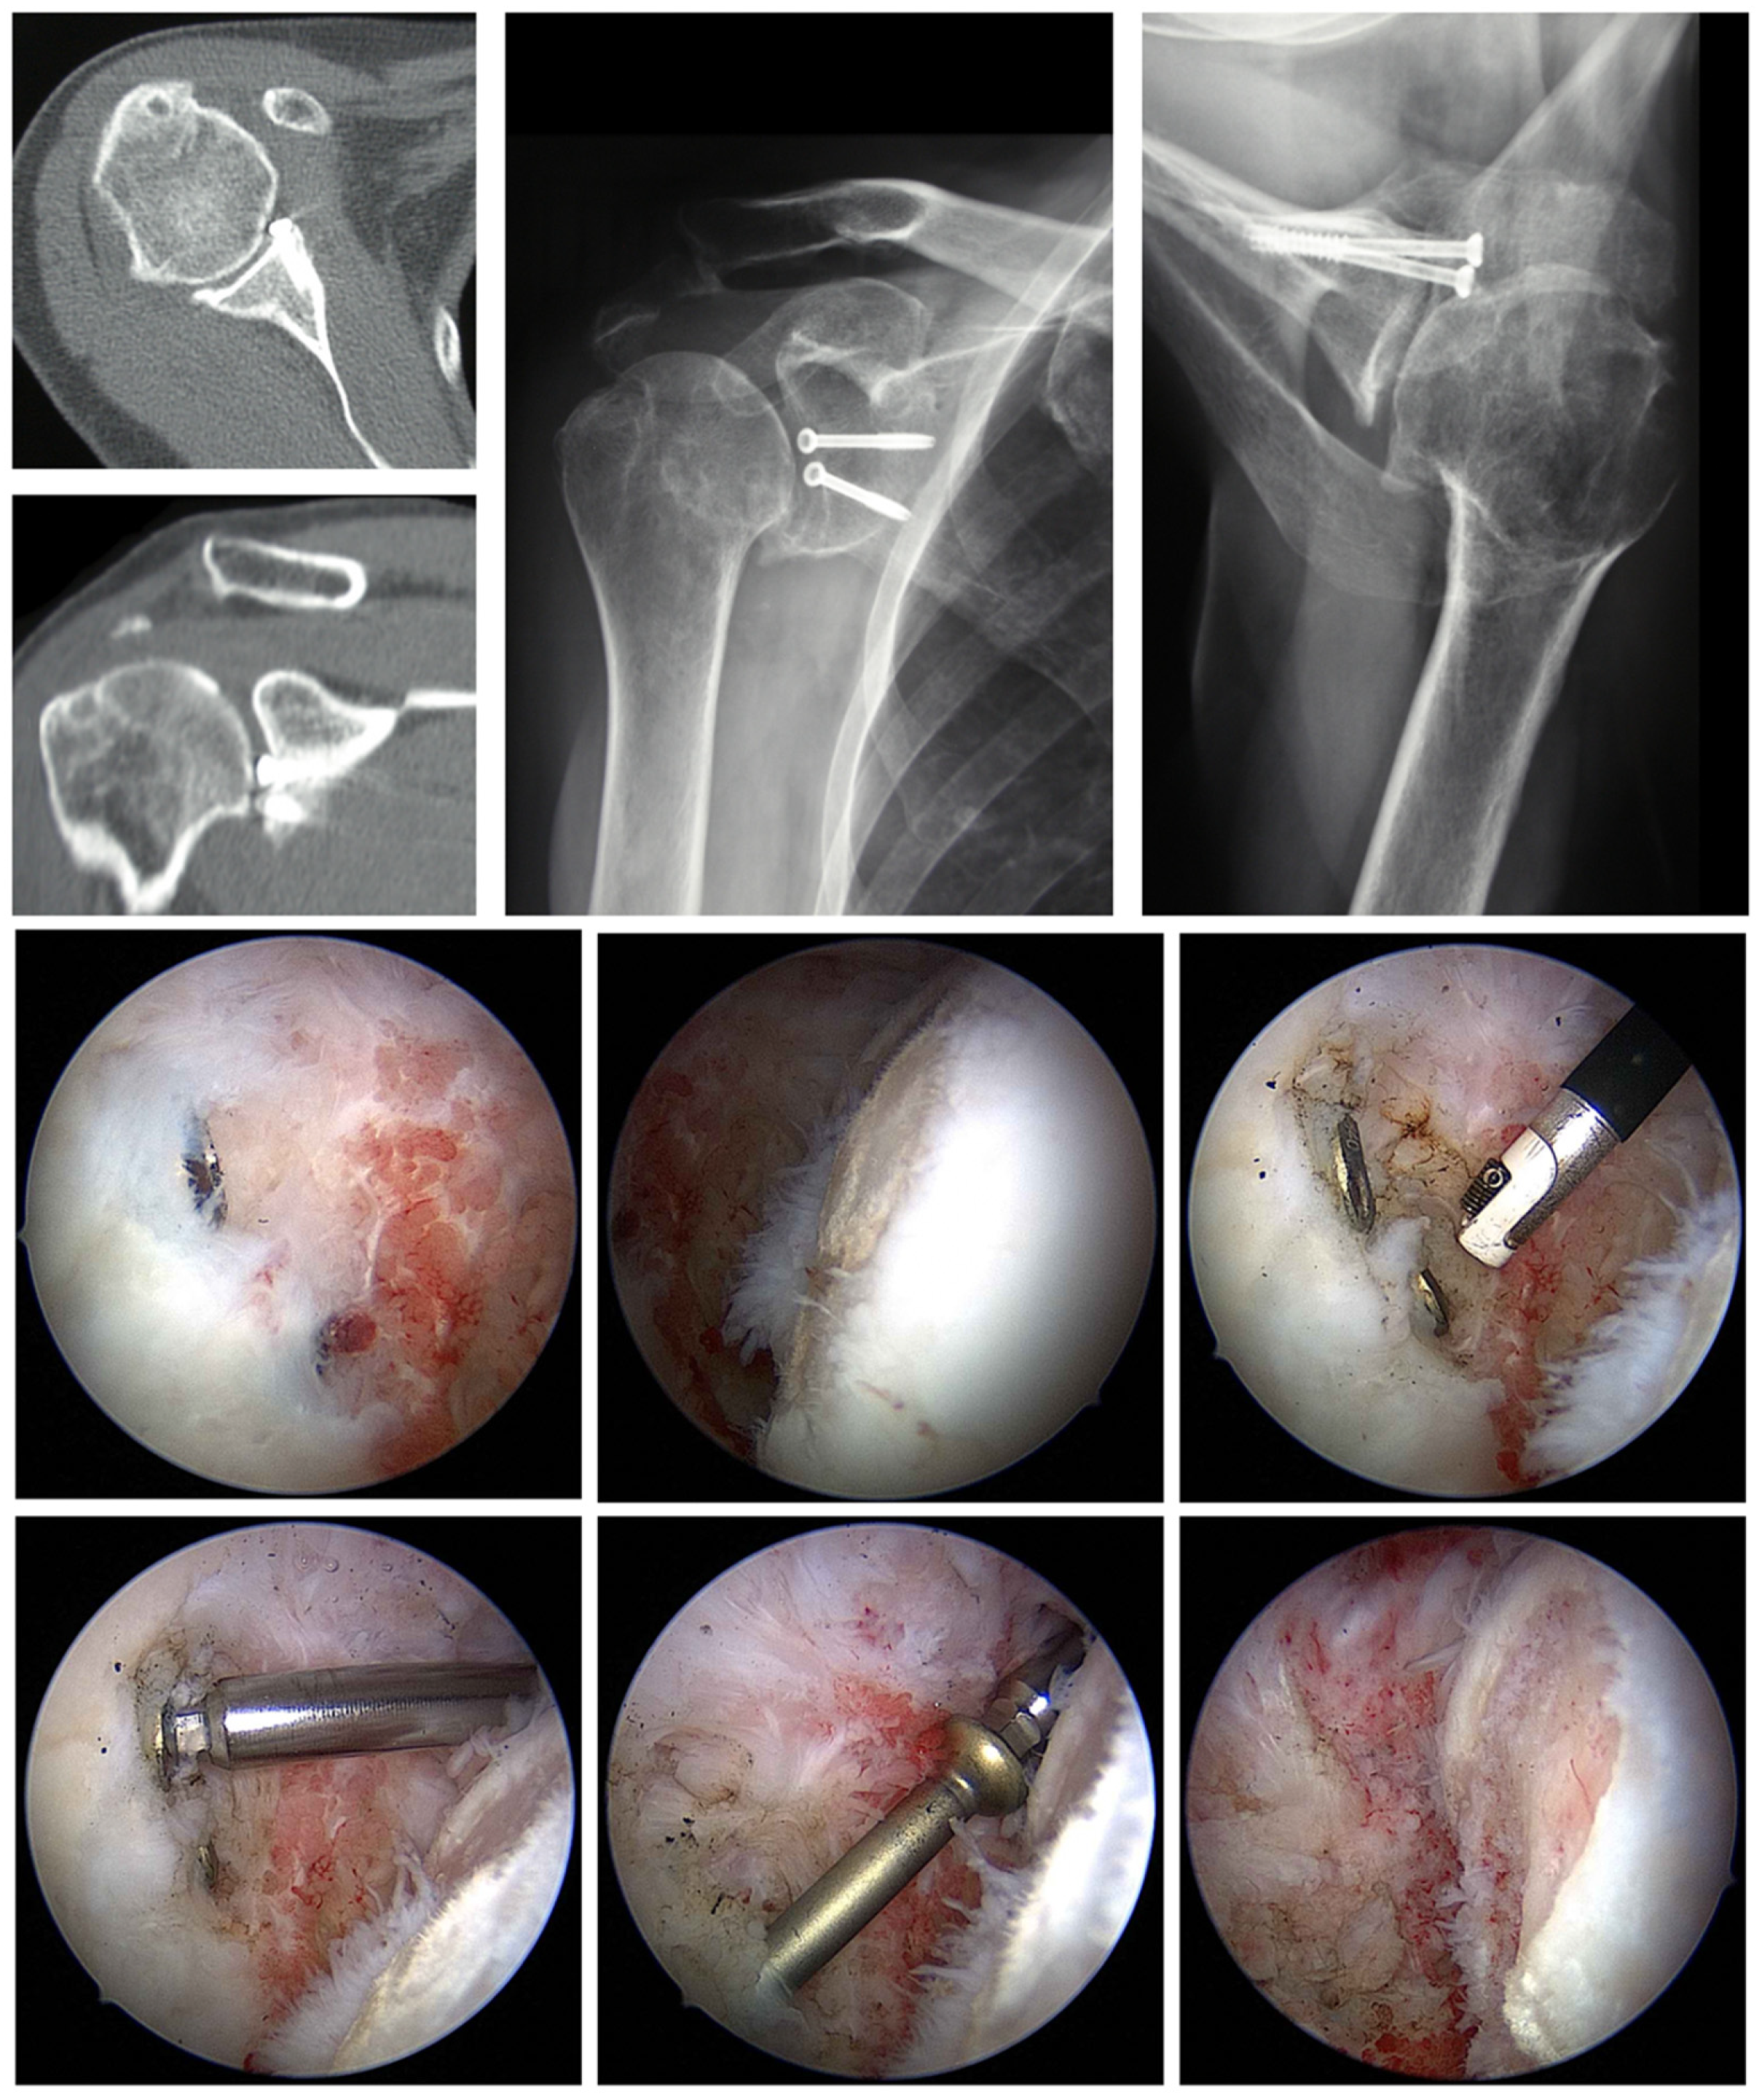

6.2. Removal of Foreign Material

6.3. Arthroscopic Debridement and Arthrolysis